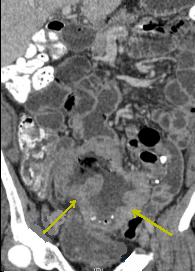

Image d'une masse

fibreuse desmoplastique retractile mesenterique (

fleche jaune ) avec des nodules de calcifies.

Diagnostic de tumeur

carcinoide : Masse tumoral particuliairement de

l'intestin , image de metastase , et syndrome de

secretion serotonine :

Diarrhee , HTA ou hypoTA

de persitante , tachycardie et bronchospasme |

Image de tumeur

multicentrique avec masse a hyper -dense nonhomogene

spidiculee mesenterique et calcifiee . Tumeur

carcinoide .( Image TDM en coupe coronal ) |